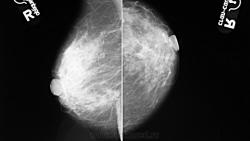

- https://radiomed.ru/sites/default/files/styles/case_slider_image/public/user/1787/P1010698.JPG?itok=qOpfbR3n

- https://radiomed.ru/sites/default/files/styles/case_slider_image/public/user/1787/P1010699.JPG?itok=-hMVVlD6

На фоне фиброзной мастопатии определяются с обеих сторон рассеянные микрокальцинаты и мелкие стромальные, а справа в в/н квадранте подозрительные сгруппированные - нужна пункция